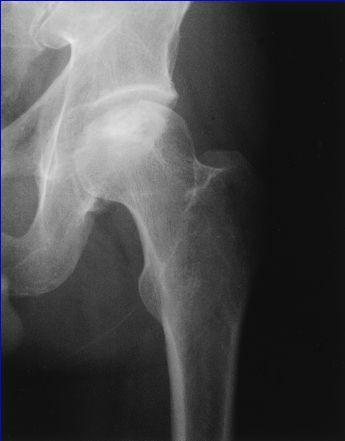

Secuencias Radiológicas

SE APRECIA UNA LINEA DE COLAPSO SUBCONDRAL EL SIGNO DE LA MEDIA LUNARADIOLOGIA NORMAL EL DIAG SE PUEDE REALIZAR POR RESONANCIA MAG

COLAPSO AFECTA LA SUPF SUBCONDRAL PERDIENDO SU MORFOLOGIA NORMAL

LA INCONGRUENCIA ARTICULAR PRODUCE PERDIDA DEL GROSOR DEL CARTILAGO Y CAMBIOS EN EL ACETABULO